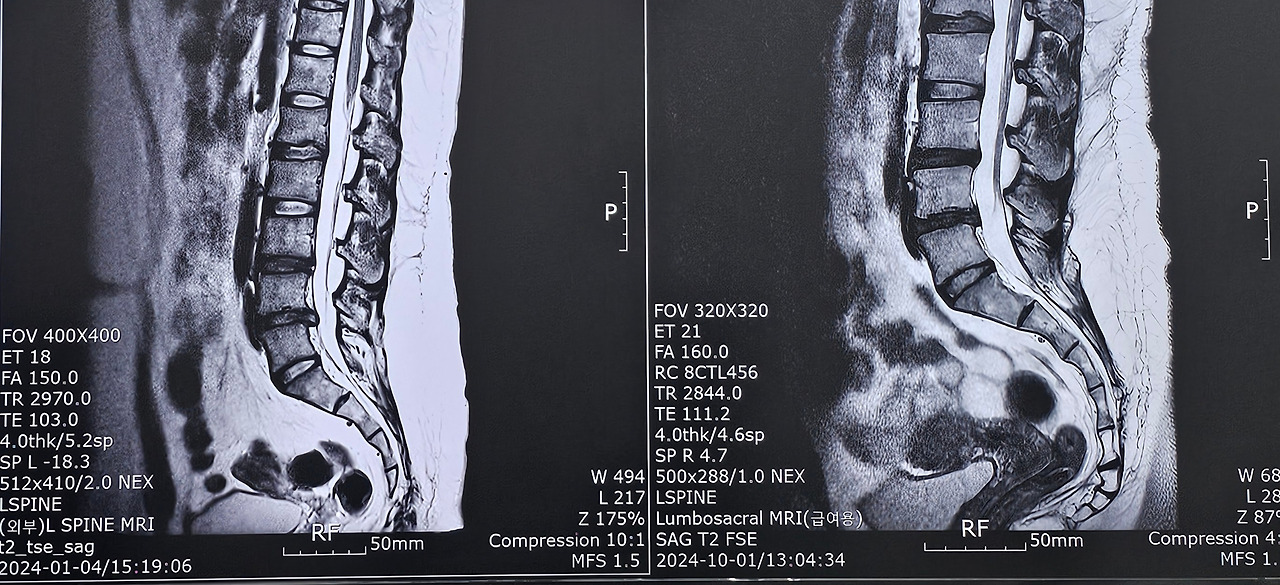

나는 4-5번 디스크가 튀어나왔고, 당시에는 화장실을 갈 수도 없었다. 하지만 9개월이 지난 24.10월 경에는 칼로 자른 듯하게 흡수된 것을 알 수 있다.(이것도 찍는 단면에 따라서 다를 수 있다곤 한다.) 여전히 움직이거나 걷는 것, 오래 앉아있는 것에는 제약이 있다. 흡수된 부분도 있지만 3-5번까지가 다 퇴행된 상태라 평생 완치는 없다고도 한다.